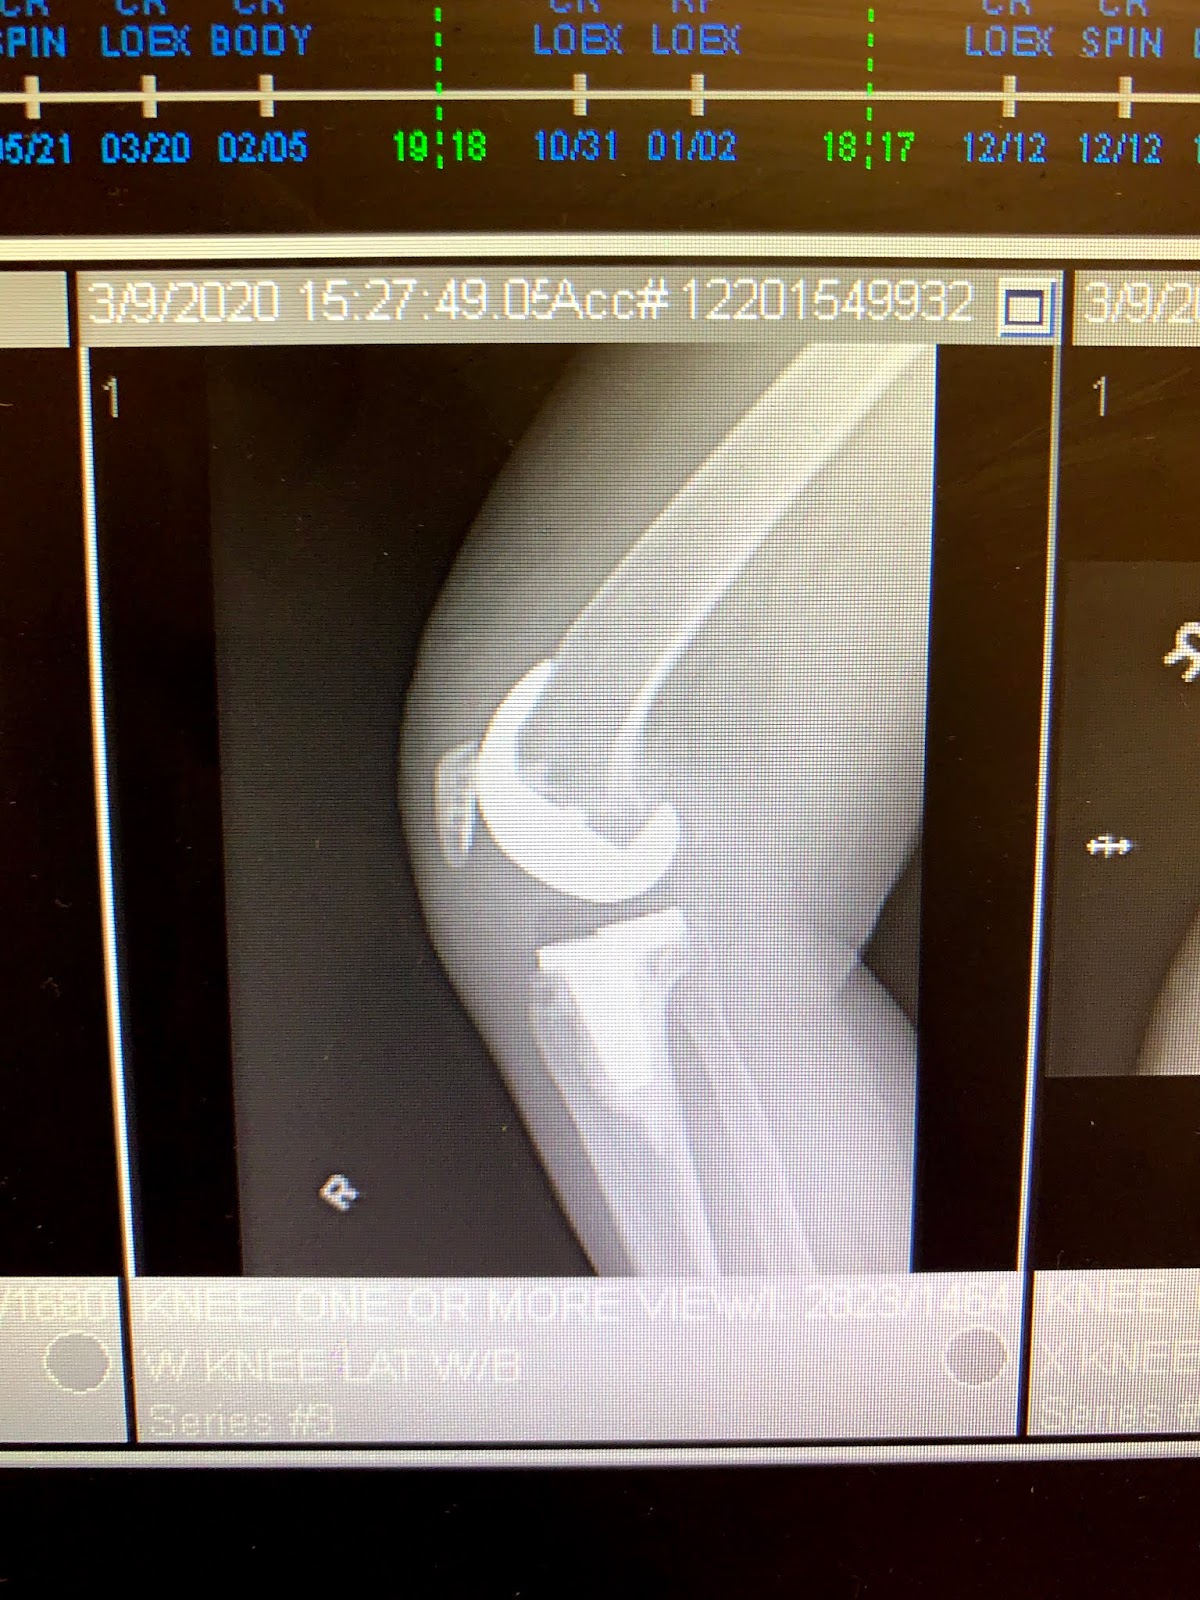

Per them: X-rays look perfect. Surgery scar looks perfect. Pain is very minor today.

Front of knee. They replaced the ends of my bones with surfaces made of chrome, titanium, and something, cemented in place, then put a pad in between to replace the cartilage that hasn’t been there for a very long time.

Some kind of plasticky stuff.

Side: and, yes, that’s my original patella hanging out at the front of my knee.